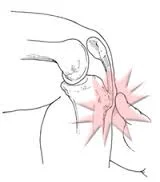

O stress repetitivo da contração do quadríceps é transmitida através do tendão patelar para a tuberosidade da tíbia imaturo. Isso pode causar micro-fraturas por avulsão (arrancamento) associado a um processo inflamatório do tendão, levando ao crescimento ósseo em excesso na tuberosidade e produzindo uma protuberância visível que pode ser muito doloroso quando tocado e atividades, tais como ajoelhar, correr, jogar futebol, handball, volley, basquete, lutar e dançar. Tipicamente, a síndrome desenvolve-se lentamente com períodos de melhoria e piora alternantes e sem trauma ou outra causa aparente, no entanto, em alguns casos, até 50% dos pacientes dos pacientes relatam uma história trauma (contusão) desencadeando os sintomas.

A condição é geralmente auto-limitante e é causada pelo stress no tendão patelar que liga o músculo quadríceps na parte da frente da coxa para a tuberosidade tibial anterior, que ocorre na fase de “estirão de crescimento” do adolescente. Por isso, é muito comum ortopedistas orientarem os pais que a condição vai melhorar com o final do crescimento. Apesar de muitos orientarem o afastamento de atividades esportivas, particularmente, costumo detectar e corrigir distúrbios biomecânicos como encurtamento muscular de isquiotibiais (posteriores de coxa), fraqueza e perda da capacidade de dissipação de energia cinética de quadríceps (anteriores de coxa) e de glúteos médio e mínimo na quadril e orientar quanto a possíveis erros de treino, sendo mais comum exageros de volume e frequência de treinos.